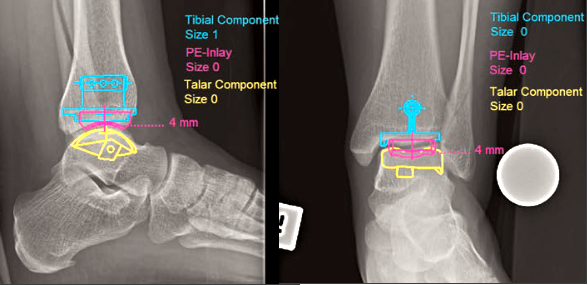

1. Chuẩn đoán bệnh lý khớp cổ chân - Ankle joint

Chức năng này cho phép phát hiện bệnh lý tại khớp cổ chân. Tất cả các tùy chọn đo lường từng phần cũng như các lựa chọn của implant đều có sẵn.

Chức năng này tự động tính toán các góc độ liên quan để phân tích tình hình trước khi phẫu thuật. Kết quả sau phẫu thuật có thể được mô phỏng bất cứ lúc nào.